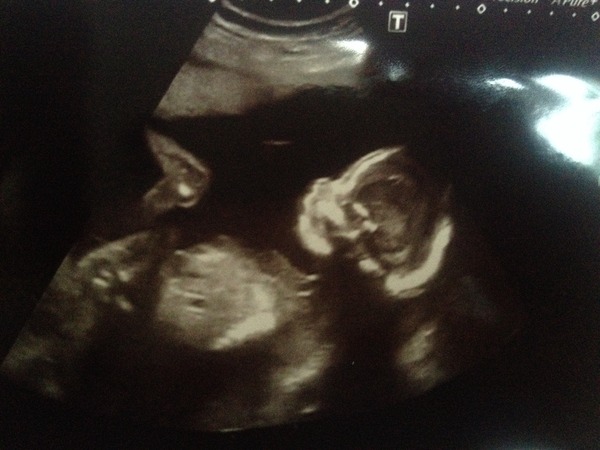

Hello peeps, scan just finished and very happy that we're team pink, sonographer was awesome so very thorough, the pictures I got were very cute and the profile one is actually really pretty Smile

PopcornFrenzy · 02/07/2014 13:25

Profile picture for you :)

That's a lovely picture popcorn!

That's such a good picture popcorn!!

Ahhhhh lovely pic!!!! Ours were all rubbish, they didn't charge us and I think that's why.

Hello from sunny Lanazrote, ladies! Grin Scan picture lovely Popcorn, have attached ours too hopefully. Dire flight as I have managed to catch a horrible cold and was hell on my sinuses but nice to be here and not have to do anything! Bit of stretchy pain today but better than it has been. Hope it improves for you amylou, hang in there!

Gorgeous scan pics, Popcorn and Twiglet - so clear. Mine were just total fuzz, I'm amazed they could decipher anything!

What lovely scan pictures! If mine is anything to go by I will be giving birth to a very large floating head (shouldn't have said that..definite nightmares now!)